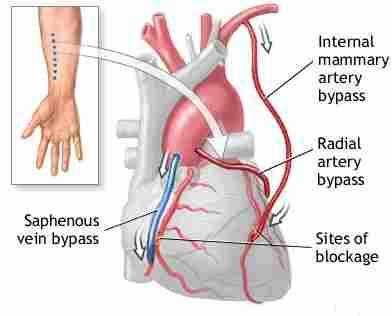

What two main arteries supply the breast?

Lateral Thoracic

Internal Mammary

Where does the Lateral Thoracic Artery arise from?

the axillary artery

Where does the Internal Mammary Artery arise from?

subclavian artery

What are the secondary arterial supplies of the breast?

Thoracoacromial artery

intercostal artery

What artery is used for the CABG procedure?

Internal Mammary